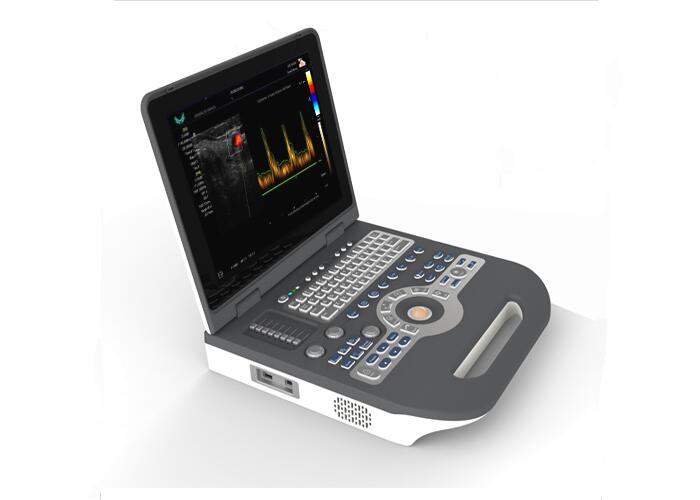

ulti - frequency Portable Ultrasound Scanner CE Approved with 15 Inch LCD Screen

1.Easy to carry,small and light with comprehensive function

2.15” HD LED display. Angle

3.2D/CFM/PDI/PW/M scanning modes

4.Integrated ultrasonic network platform,support DICOM transmit

5.Big capacity built-in lithium battery

6.Embed computer system ensure stabilization safe and fast running.

Portable Ultrasound Scanner Color Doppler Machine With 15 Inch LCD Monitor Images |